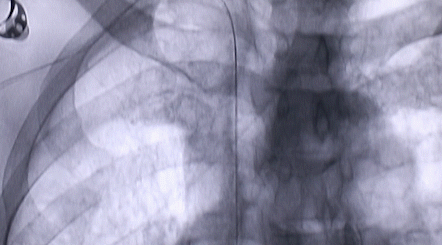

1月12日,西安國際醫(yī)學(xué)中心醫(yī)院心臟外科郭穎強(qiáng)主任團(tuán)隊(duì)成功為一名腹主動(dòng)脈閉塞、右側(cè)腎動(dòng)脈閉塞、左側(cè)腎動(dòng)脈重度狹窄、腹壁淺表動(dòng)脈側(cè)支循環(huán)形成、高血壓病3級(jí)(極高危組)合并閉塞性周圍動(dòng)脈粥樣硬化、急性腎功能不全的老年患者實(shí)施腎動(dòng)脈球囊擴(kuò)張 腎動(dòng)脈支架植入術(shù) 動(dòng)脈血栓抽吸術(shù) 髂動(dòng)脈開通術(shù),治好了困擾患者多年的頑固性高血壓?;颊吣壳翱祻?fù)良好,將于近日出院。

按照術(shù)前制定的方案,郭穎強(qiáng)主任和楊金保博士首先嘗試開通閉塞的右腎動(dòng)脈,但由于血栓機(jī)化、鈣化嚴(yán)重,右腎動(dòng)脈難以開通。遂謹(jǐn)慎擴(kuò)張狹窄的左腎動(dòng)脈,并成功植入一枚支架。之后經(jīng)過反復(fù)旋磨、抽吸,順利開通髂動(dòng)脈,但腹主動(dòng)脈閉塞段仍難以擴(kuò)通。此時(shí),患者居高不下的血壓很快恢復(fù)到正常水平。

經(jīng)過3個(gè)半的奮戰(zhàn),最令張大伯頭疼的頑固性高血壓終于恢復(fù)了正常。術(shù)后當(dāng)日,張大伯便下床活動(dòng),次日復(fù)查腎功能,尿素氮、肌酐已基本恢復(fù)正常。